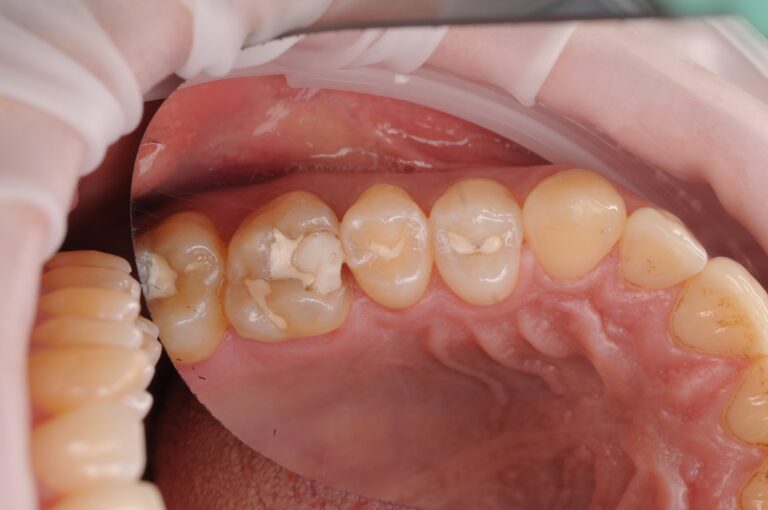

First image: a large old filling with decay already developing underneath.